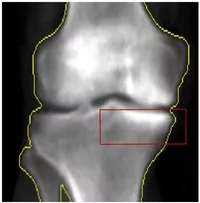

Cartilage Damage Index (CDI) Description:

a parsimonious cartilage assessment that focuses on areas where cartilage defects often develop. It includes 60 informative locations within femur, tibia, and patella compartments (medial and lateral).

CDI

Zhang M, Driban JB, Price LL, Harper D, Lo GH, Miller E, Ward RJ, McAlindon TE. Development of a rapid knee cartilage damage quantification method using magnetic resonance images. BMC Musculoskelet Disord. 2014;15:264.

Zhang M, Driban JB, Price LL, Lo GH, Miller E, McAlindon TE. Development of a Rapid Cartilage Damage Quantification Method for the Lateral Tibiofemoral Compartment Using Magnetic Resonance Images: Data from the Osteoarthritis Initiative. BioMed research international. 2015;2015:634275.